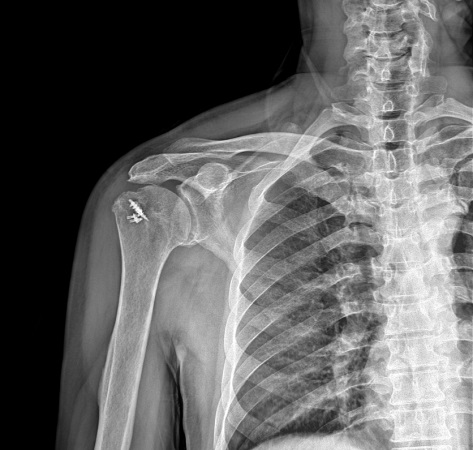

Postoperatif omuz röntgeni